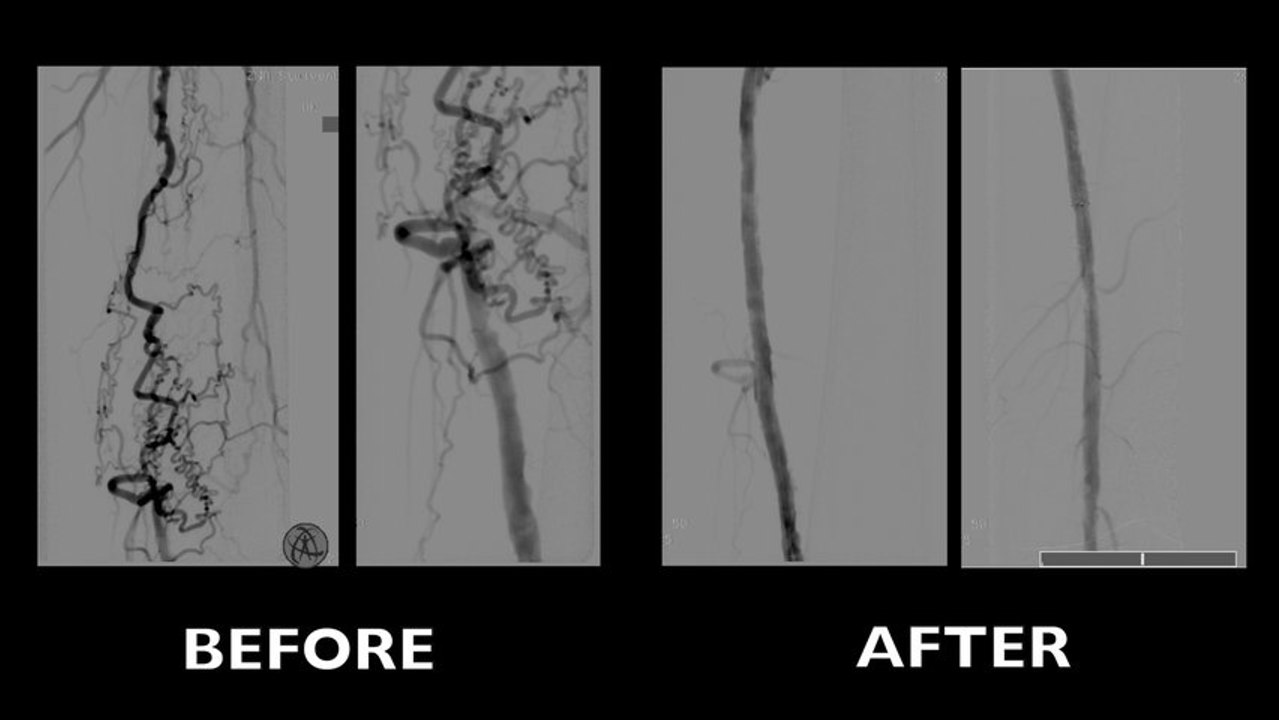

The Role of PTA and Stenting in the Treatment of Femoropopliteal disease today

Live cases from Antwerp (Belgium)

Endovascular Electronic Education (EEE) – Stent Selection for Complex SFA Lesions

Live session from Charing Cross Symposium - London, UK

Electronic Endovascular Education Program: Treatment of the SFA

Live session from LINC congress, Leipzig - Germany